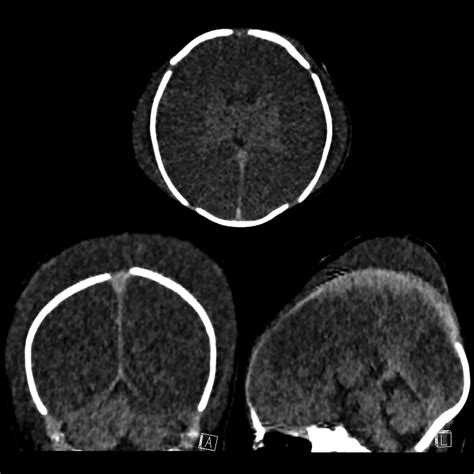

• caput vs cephalohematoma ultrasound

• caput vs cephalohematoma images